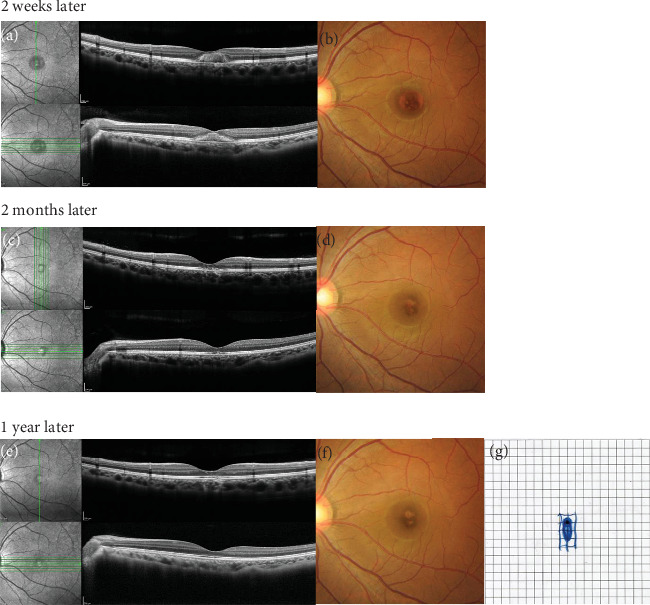

Introduction: Accidental retinal injuries caused by lasers without appropriate eye protection are not rare; most cases are unilateral. We report the case of a medical nurse who sustained bilateral foveal damage through indirect exposure to a picosecond dermal laser. Case Presentation: A 23-year-old nurse working in a cosmetic surgery clinic was using a picosecond KTP/Nd:YAG laser for tattoo removal. Because the procedure was complicated, she neglected the use of protective eyewear and experienced dazzle. Thirty minutes after starting the procedure, she developed central scotomas in both eyes. We examined her eyes the next day. Ophthalmologic examination revealed best-corrected decimal visual acuity (BCVA) of 0.6 in the right eye and 0.3 in the left eye. Spectral domain-optical coherence tomography showed a hyperreflective inner retinal layer with a lamellar defect and focal outer retinal detachment in the right eye; the left eye exhibited intra- and subretinal foveal hemorrhages. Injections of sub-Tenon's triamcinolone acetonide (12 mg/0.3 mL) in the right eye and intravitreal tissue plasminogen activator (30 μg/0.05 mL) in the left eye were administered on the same day. Two weeks later, a full-thickness macular hole (FTMH) was identified in the right eye; pars plana vitrectomy was required 6 weeks after initial presentation. Because the FTMH failed to close, a second procedure was performed 2 months later. One year after initial presentation, BCVA in the right eye had improved to 0.4. Although the FTMH remained closed, an outer retinal layer defect persisted. In the left eye, foveal hemorrhage resolved within 1 month of initial presentation. At the 1-year follow-up, BCVA in the left eye was 0.4; outer retinal layer disruption was evident at the central fovea. Conclusions: Continuous Nd:YAG laser exposure during cosmetic procedures likely caused the bilateral foveal damage observed in this case. All individuals using lasers must be aware of the importance of protective goggles.